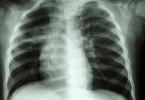

• 右肺高密度影是什么意思?

右肺高密度影是什么意思?

右肺高密度影通常指影像学检查中右肺组织出现异常增白的区域,可能由肺炎、肺结核、肺结节或肿瘤等疾病引起。需结合临床表现和其他检查进一步明确诊断。1、肺炎细菌或病毒感染可能导致肺部炎症反应,形成高密度影。 ...